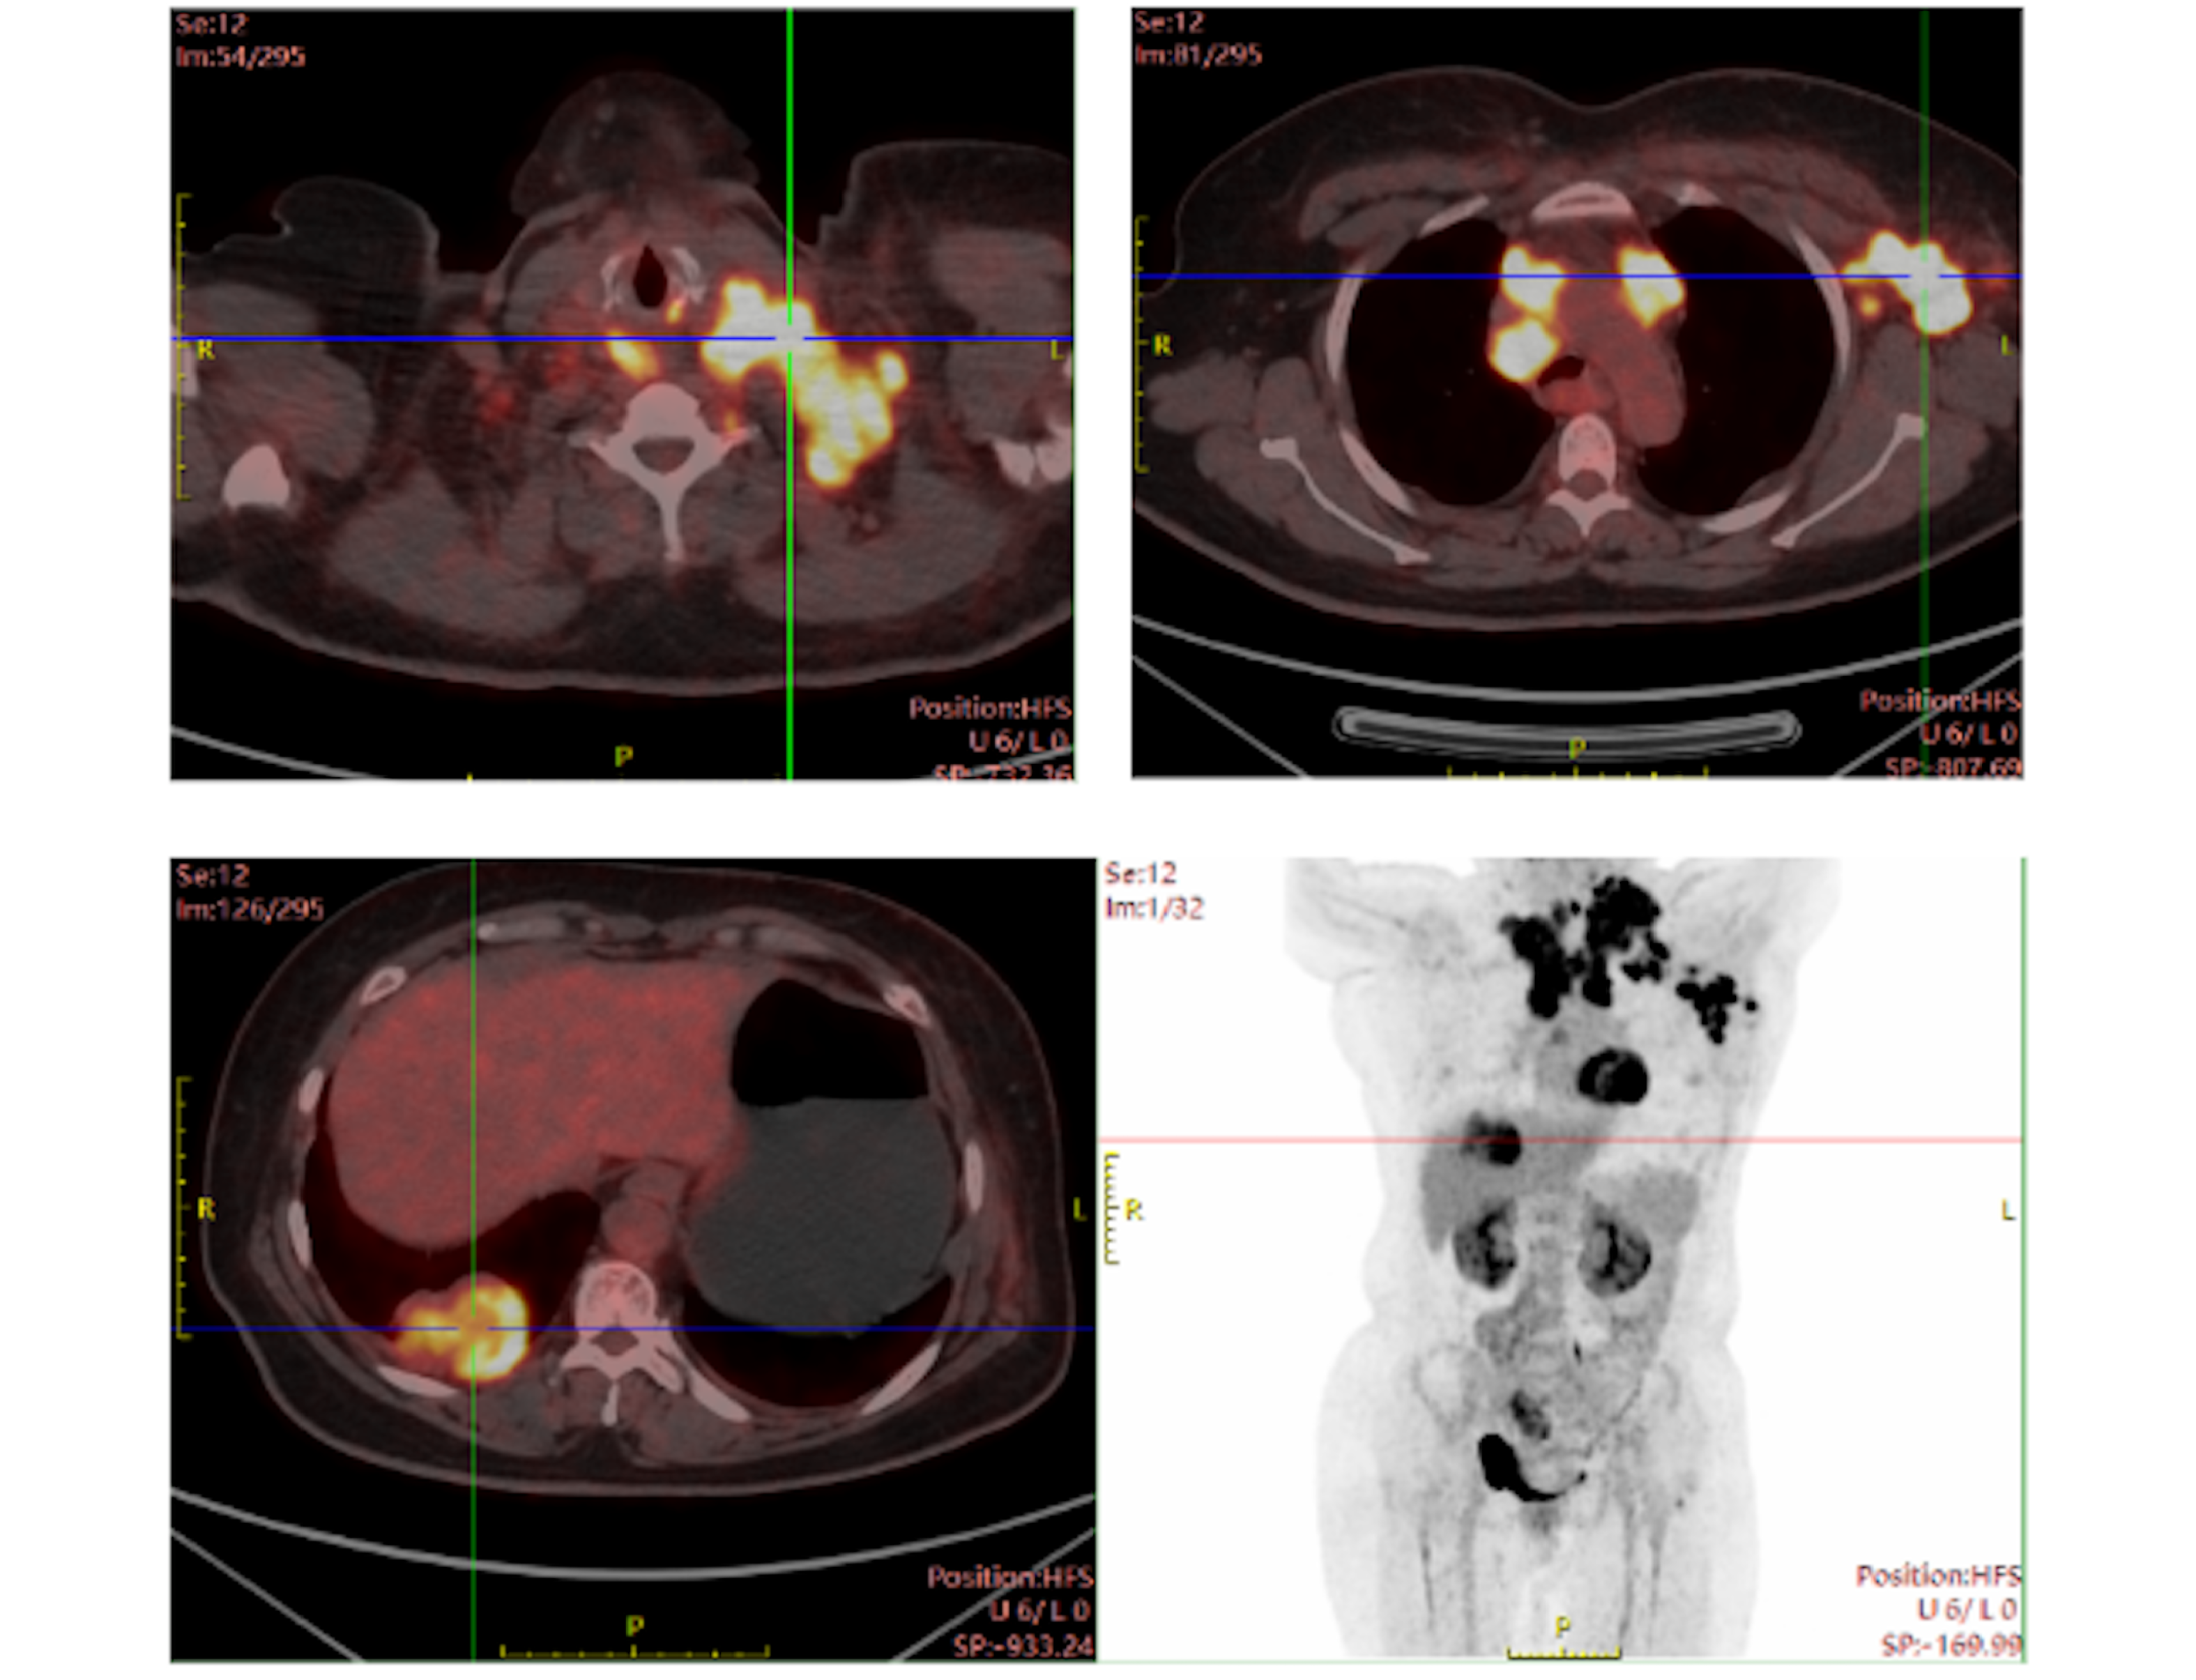

Xiaotong Qiu, Liangkun You, Chongwei Wang, Jin Sheng

SMARCA4-deficient non small cell lung cancer (SMARCA4-dNSCLC) has recently garnered increasing attention due to its high malignancy and poor prognosis. The literature suggests that in non small cell lung cancer (NSCLC), the loss of SMARCA4 frequently co-occurs with mutations in KRAS, KEAP1, and STK11 rather than in EGFR, ALK, and ROS1. Herein, we present the first documented case of SMARCA4-dNSCLC accompanied with rare mutations of EGFR exon 20 S768I and exon 18 G719X. The patient achieved partial response with afatinib for 17 months. Our case highlights the importance of EGFR mutations in the precision targeted treatment of SMARCA4-dNSCLC.